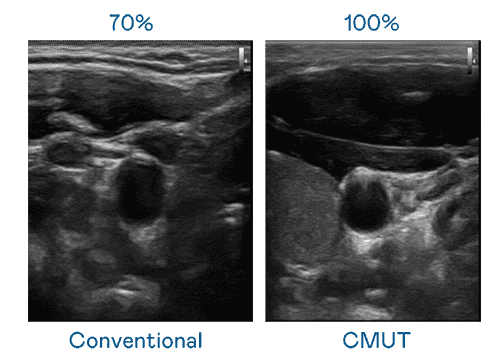

CMUT 技术是一种用电容式微机电元件来产生超音波讯号的技术。。与传统 PZT 压电式技术相比,,CMUT 频宽增加 30%,,,,更宽频的超音波讯号让影像解析度大幅提升,,是实现高影像品质医疗超音波扫描、、促进精准医疗发展的关键技术。。。

大频宽带来超清晰影像

超音波影像的解析度高低,,,首先取决于探头能发出的讯号频宽。。尊龙集团 CMUT 可提供高清晰的超音波讯号,,提供高频宽、、、高灵敏度、、、影像纹理细节更高的超音波影像,,,协助医护人员缩短影像判读时间及利用精准的医疗影像进行诊断。。。